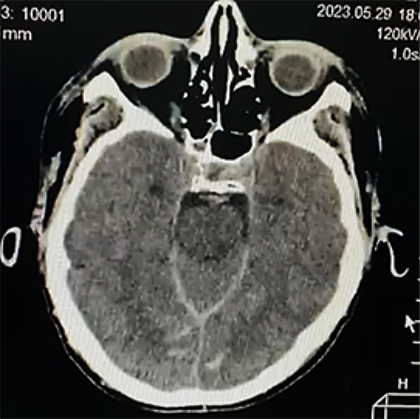

Paciente femenino de 52 años, proveniente y residente de Cochabamba, provincia Quillacollo, acude al servicio de emergencia del Hospital Obrero Nro. 2 de la Caja Nacional de Salud; con antecedentes de diabetes mellitus tipo 2, hipertensión arterial, enfermedad renal crónica, estadio 5 en hemodiálisis y un accidente cerebrovascular hemorrágico hace 1 año; es medicado con metformina 850 mg, carvedilol 12,5 mg, losartan 100 mg, alfa metildopa 500 mg y recibe hemodiálisis desde hace 1 año, trisemanal; presenta un cuadro clínico de 8 horas de evolución caracterizado por cefalea holocraneana, pulsátil, súbito, de intensidad moderada, acompañado de somnolencia, entumecimiento a nivel de columna cervical-dorsal, paraparesia de extremidades inferiores y una escala de coma de Glasgow de 11-12/15. Ingresa por emergencia en mal estado general, con tendencia a la hipertensión PA: 231/174 mmHg, PAM: 183, FC: 96 latidos/min. Saturación de oxígeno 91% aire ambiente. Se solicitan algunos laboratorios: Glicemia 380 mg/dl, creatinina 6,9 mg/dl, sodio: 129 mEq/l (Tabla 1); rápidamente se solicita una tomografía axial computarizada de cráneo (TAC) simple (Figura 1a, b).